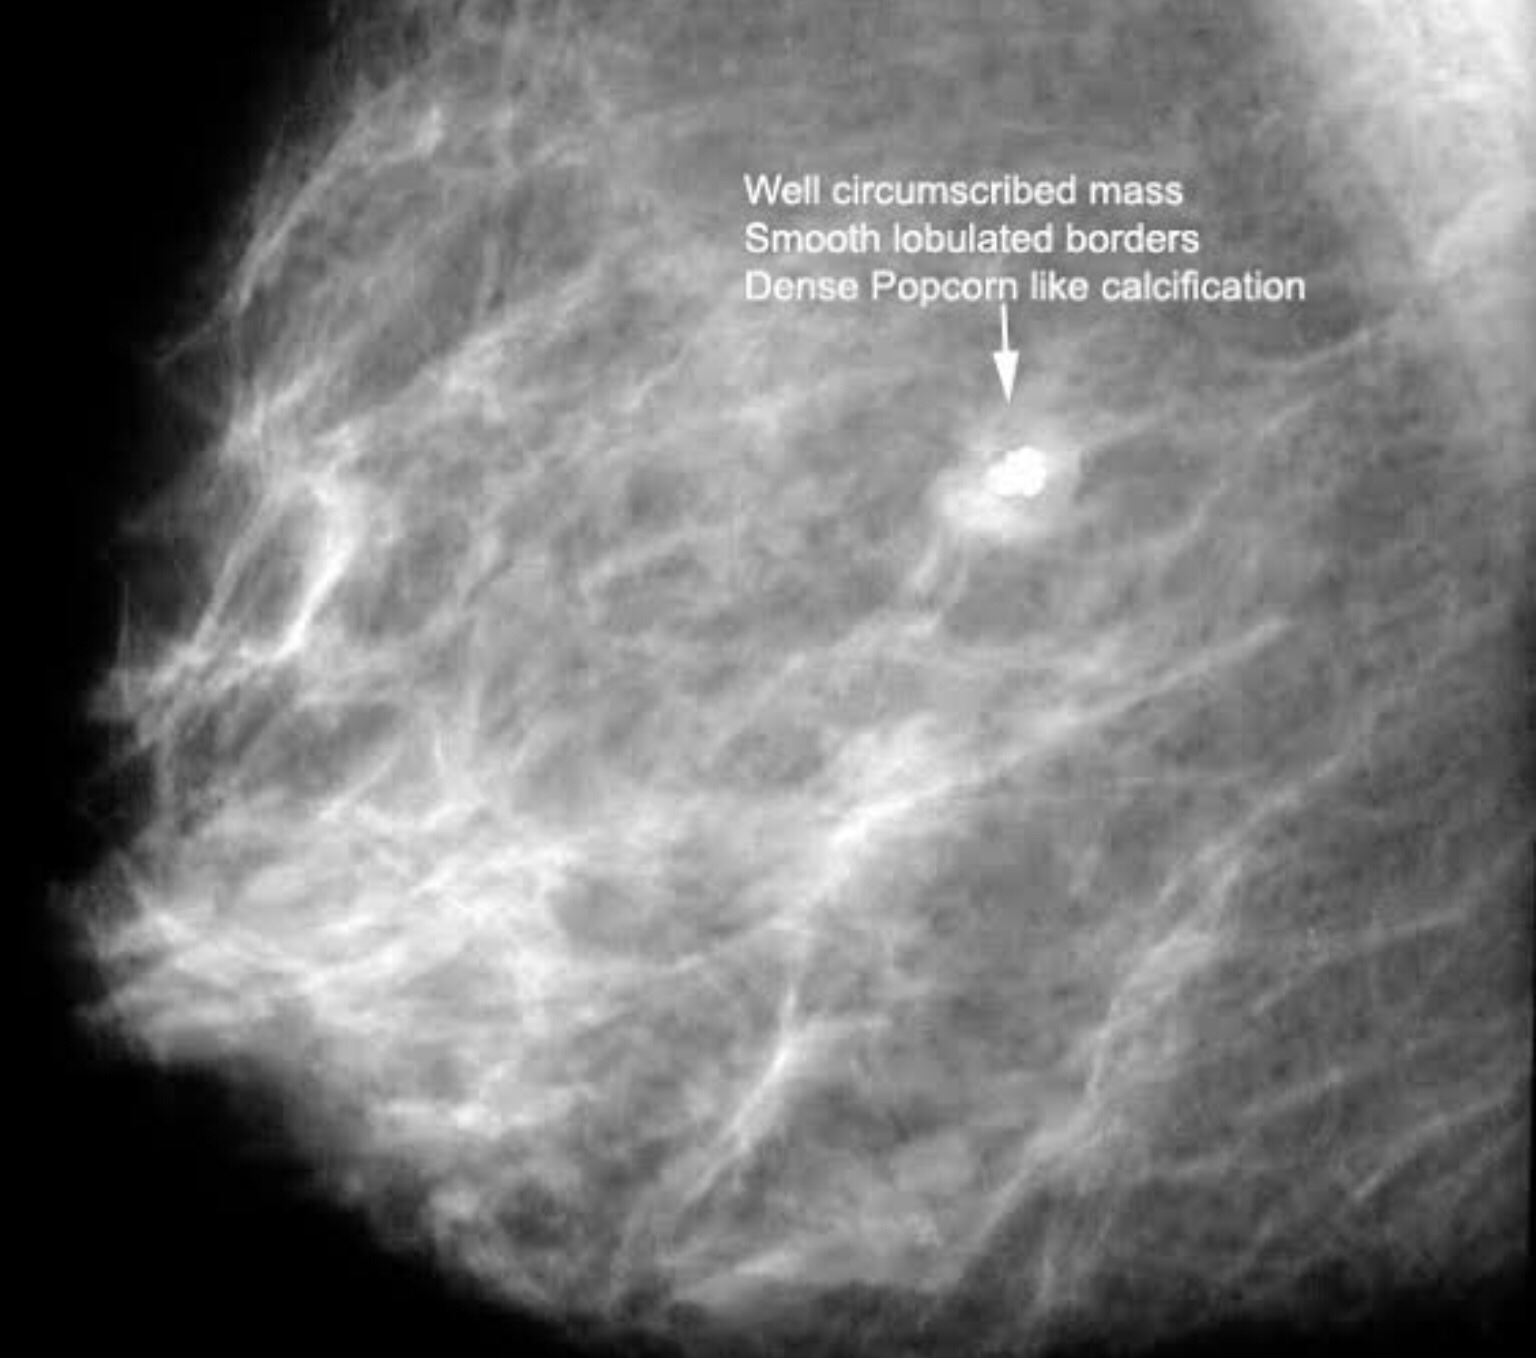

3. Description of abnormalities: Density of breasts and calcific spots. Finely granular, popcorn like, vascular calcification suggest benign disease where as spiculated lesions, lesions with pleomorphic calcifications ( varies shapes and sizes), V or Y shaped calcifications would suggest an underlying neoplastic process.

Fibroadenoma- is referred to as the Breast mouse- most often is detected as a small lump that moves inside the breast. They may be single or multiple as on the picture on the right below! The lumps are smooth walled and well defined.

The picture to the left shows a “popcorn” calcified Fibroadenoma.

B – popcorn calcification